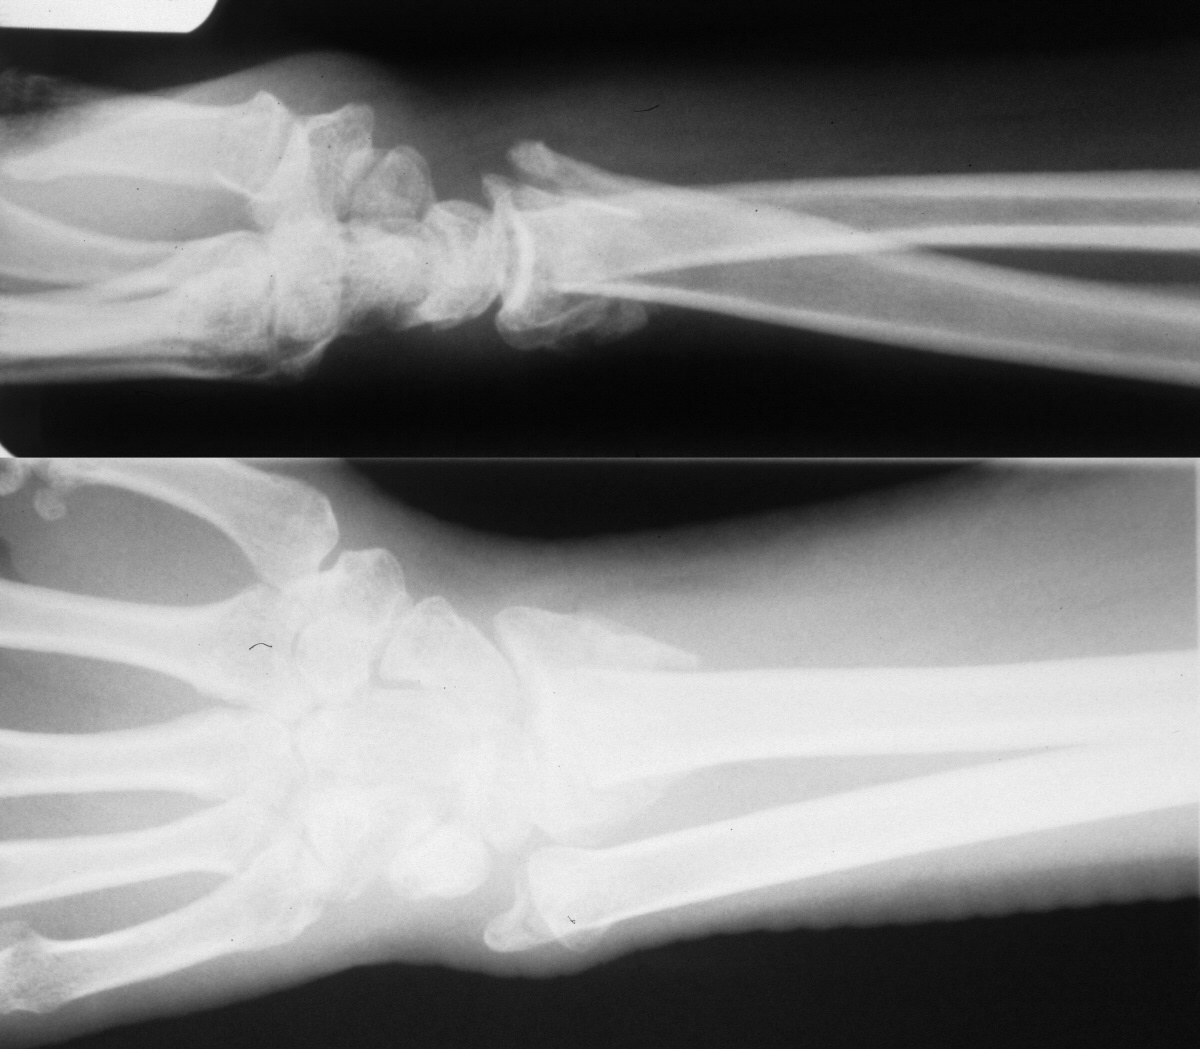

| This patient sustained a

closed distal radius fracture treated in another country. |

| Initial treatment was closed reduction and casting. 18 months later, she presented with loss of forearm supination past neutral and ulnar head prominence and pain. |